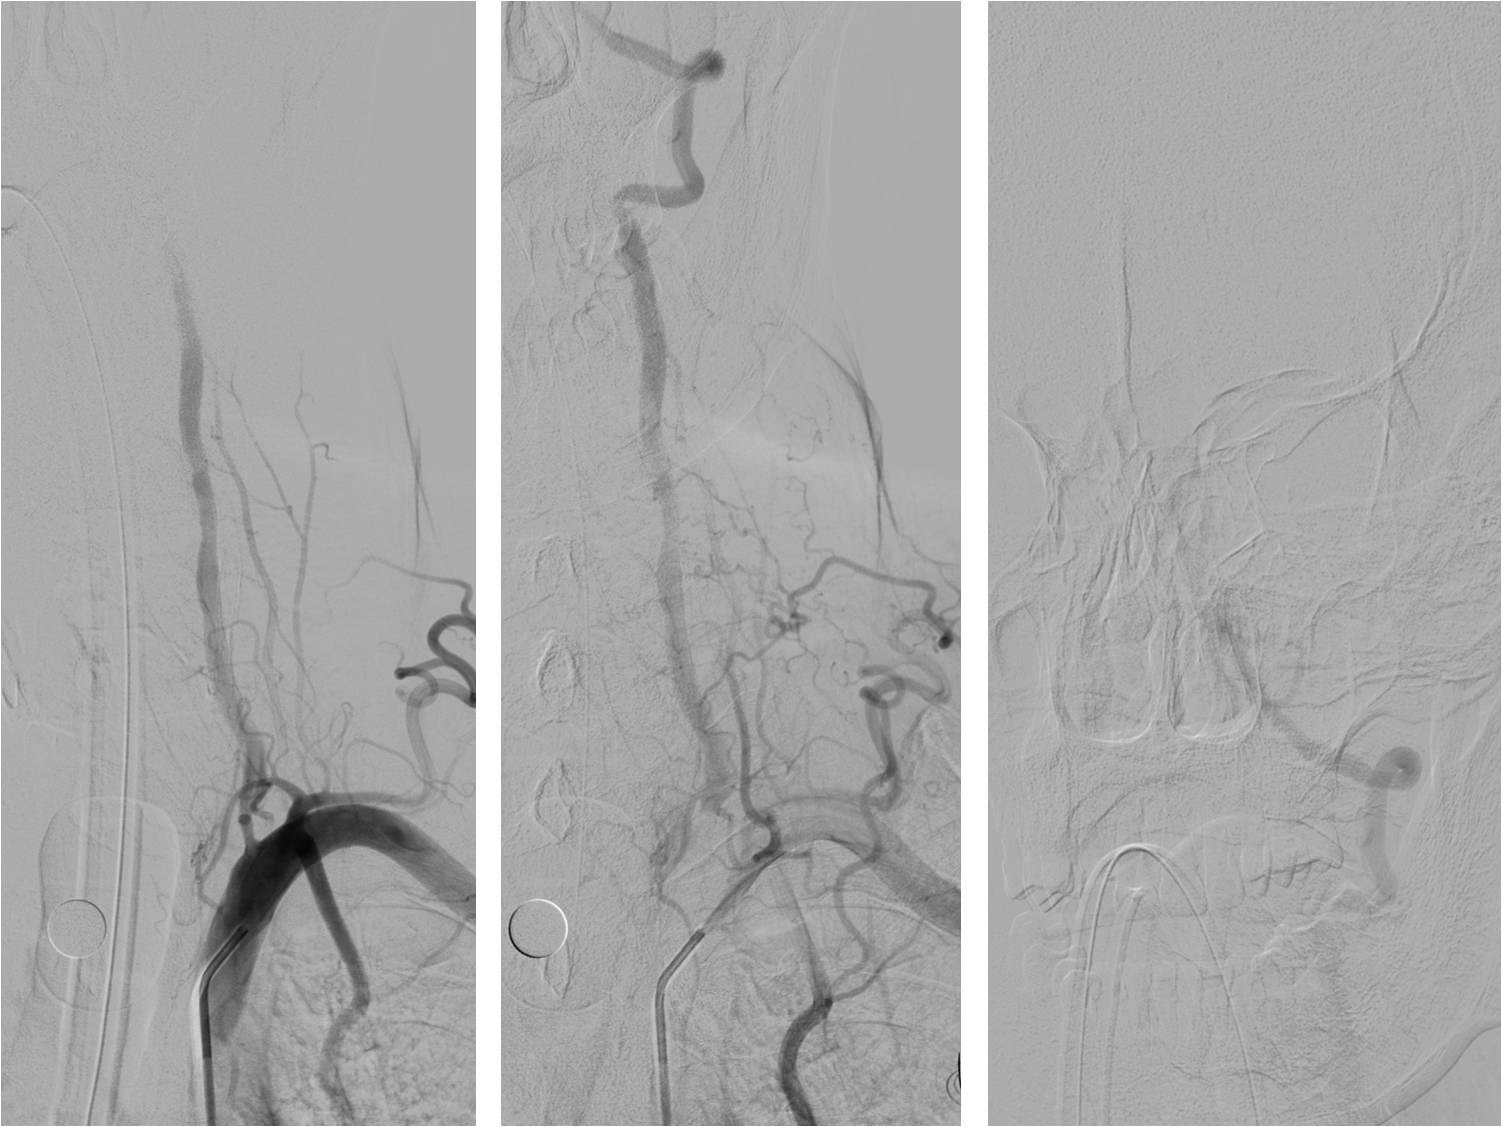

Case6 术后呼吸功能衰竭

》54岁,男,既往脑梗死、高血压病、糖尿病

》因头晕伴呕吐2天,9:50到达急诊

》10:08完成头CT检查

》15:30突发心跳骤停,行心肺复苏、气管插管

》NIHSS 30分

》15:55头MRA检查

》17:00行股动脉穿刺

》18:50结束手术

》术后24h NIHSS 10分

▼左椎动脉颅内段闭塞,脊髓前动脉代偿

▼右椎动脉颅外段闭塞

▼取栓后左椎动脉V4段残留狭窄

▼球囊成形,狭窄改善,不能维持

▼Wingspan支架置入